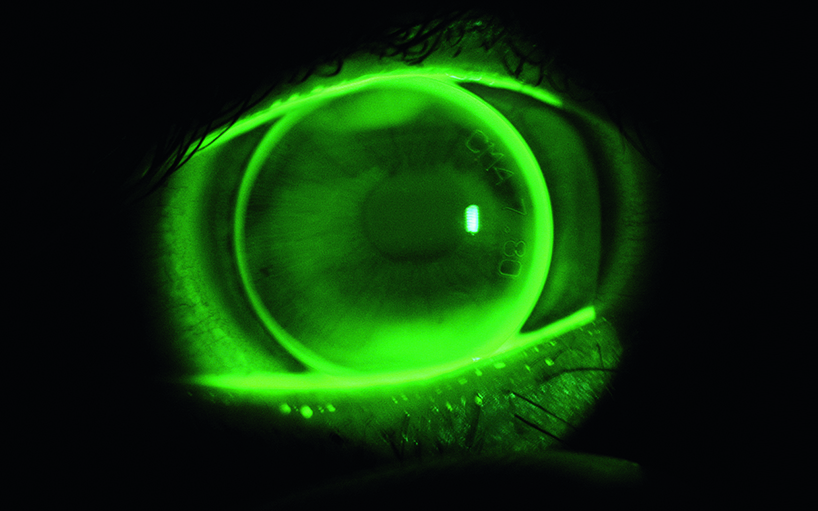

• Research on the anterior segment of the eye

Dry eye disease | cornea sensitivity | contact lenses adjustment | cornea as an optically refracting medium

The Institute of Optometry (FHNW) is involved in several projects for the development of intra-corneal lenses created by Neoptics.